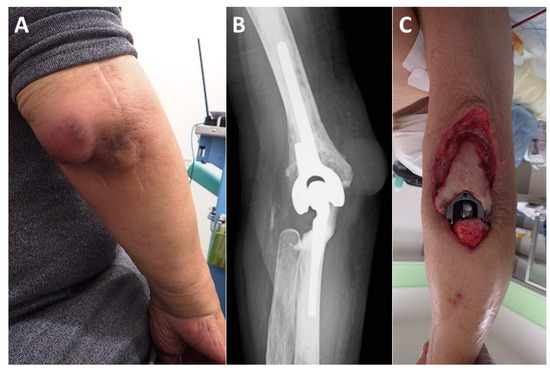

Figure 1.

Classification of soft tissue defect locations around the elbow. The elbow is divided into four zones by drawing a line connecting the center of the humerus and the brachial artery (BA), and a perpendicular line to it: A (anterior), M (medial), P (posterior), and L (lateral).

Figure 3.

Representative case (Case 6). The patient is a 74-year-old male with rheumatoid arthritis. (A): Four years after total elbow arthroplasty, the patient developed an infection. (B): Plain radiographs show no evidence of implant loosening. (C): Despite multiple debridements and antibiotic therapy, which successfully controlled the infection, a large soft tissue defect developed on the posterior aspect of the elbow. (D): On the 14th day after the initial surgery, a free ALT flap was performed using the BA as the recipient vessel (flap size: 90 cm2). The flap pedicle vessels (dotted line) were guided through a spacious subcutaneous tunnel to the anterior aspect of the BA. (E): The flap pedicle vessels were aligned parallel to the BA and accompanying brachial vein (BV), ensuring a smooth transition towards the defect site (BA diameter: 5.5 mm, flap pedicle diameter: 1.5 mm). The anastomosed artery (hashmark) and vein (asterisk) can be seen bulging over the BA and accompanying vein. (Me; median nerve). (F): Ultrasound imaging at three weeks postoperatively shows a well-expanded anastomosis (hashmark). (G): Color Doppler imaging reveals no turbulence at the anastomosis site, with adequate blood flow in both the flap vessels and the distal recipient vessels. (H): The soft tissue defect is adequately covered by the ALT flap. (I): No postoperative complications were observed, and at the final follow-up one year after surgery, the patient had an elbow extension of −20° and flexion of 145°, with a “Good” outcome.

All patient and flap background data are presented in Table 1. Among the seven cases of elbow reconstruction, four were due to trauma, two were due to infection, and one was due to post-traumatic joint contracture. The locations of the free flaps were as follows: two were confined to the anterior region (A), one to the lateral region (L), one to the posterior region (P), one spanned the anterior and lateral regions (A and L), one spanned the anterior and medial regions (A and M), and one extended from the anterior to the medial and posterior regions (A, M, and P). The flap types used were ALT in four patients, LD in two, and a vascularized fibula graft (VFG) in one. The recipient vessels in all cases were the BA and its accompanying veins. In Case 1, where a VFG was performed in the lateral region (L), the short pedicle required adjusting the heel position during the anastomosis to relieve tension on the vascular anastomosis site (Figure 2F).